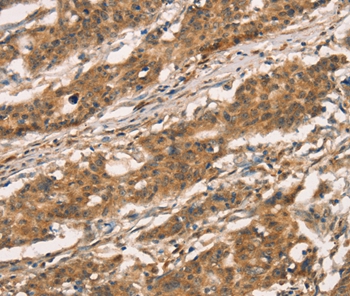

Immunohistochemical analysis of paraffin-embedded Human gastric cancer tissue using #36380 at dilution 1/30.